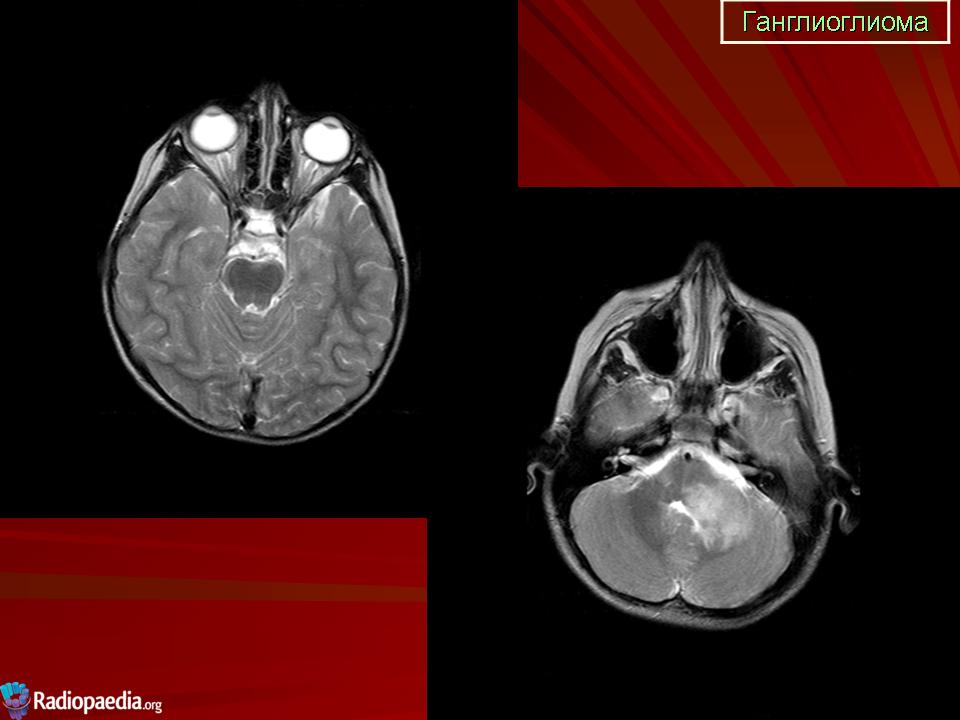

Ганглиоглиома — бифракционная опухоль, состоящая из элементов ганглиоцитомы и пилоцитарной астроцитомы. Локализуется преимущественно в полушариях головного мозга. Макроскопически представляет собой плотную четко отграниченную от ткани мозга опухоль, которая нередко содержит кисту.

Ганглиоглиома

Продолжение.